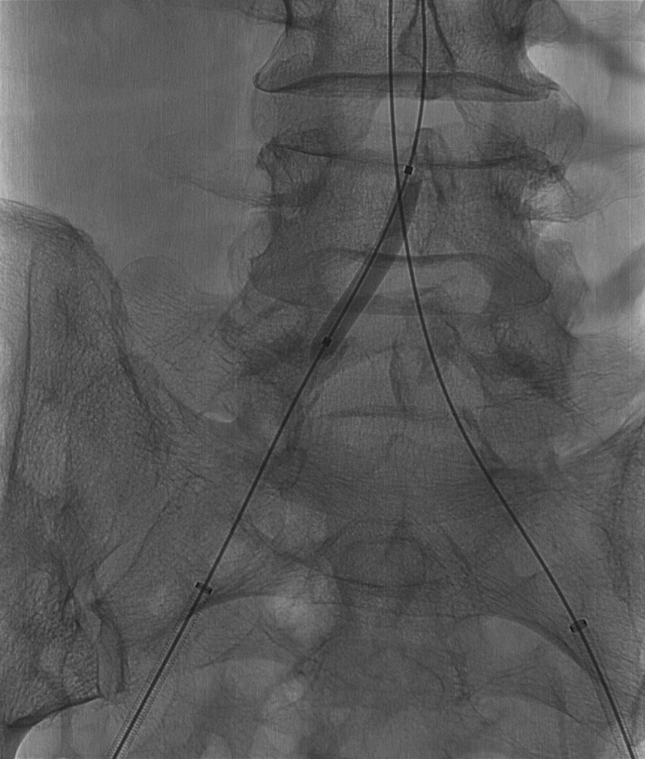

(5) 行双侧髂总动脉“对吻”支架植入术,并双侧导入INVETEC 12*40mm行双侧髂总动脉支架内近端行球囊扩张。

导丝怎么扩【问术ASK】佟铸教授:双侧髂总动脉“对吻”球扩覆膜支架植入术_https://www.jmylbn.com_新闻资讯_第7张